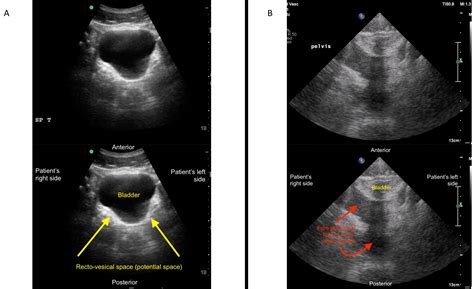

• EFAST (Extended Focused Assessment with Sonography for Trauma): This is a comprehensive ultrasound examination used to evaluate patients with trauma. It includes views of the heart, lungs, abdomen, and pelvis to detect fluid collections, pneumothorax, and other injuries.

• Focused Abdominal Ultrasound: This evaluates the abdomen for free fluid, organomegaly, and other abnormalities.

• Trauma Assessment: In trauma patients, the Fast Exam Ultrasound helps identify internal injuries, such as hemoperitoneum, hemothorax, and pericardial effusion.

• Abdominal Evaluation: It helps identify free fluid in the abdomen, organomegaly, and other abnormalities.